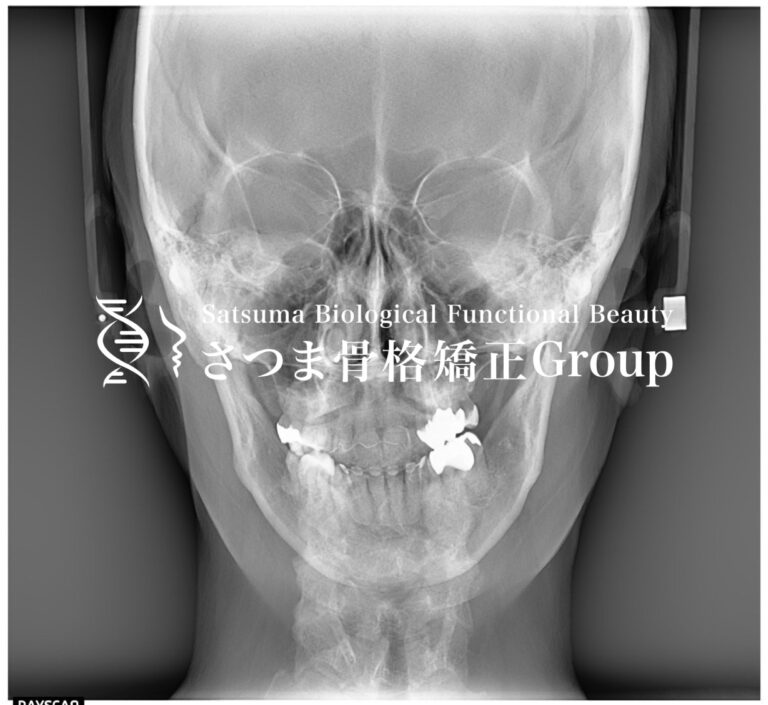

〜正面から〜

お顔の正面画像の分析について

例えば、正面からだと

正面からのセファロスタンドを使った分析では…

・顎の偏位(縦の赤い線で顎の左右のズレの確認)

・鼻背の歪みや鼻翼の左右差(縦の赤い線で上顎から鼻の歪みの確認)

・頸椎の歪み(縦の青い線で首の左右差の確認)

・フェイスラインやエラの左右差(縦の黄色い線で頬、下顎や筋肉量の左右差の確認)

・目や頬や口角の高さの左右差(横の緑の線で各部位の位置の確認)

・その他、ほうれい線の左右差や眉の高さ、肩の高さ…etc

これらを分析してさらに実際の触知や開口時の顎の動きを見ていくことで、顎関節の動きからの関節性の歪みや咀嚼筋・表情筋の使い方からの筋肉性の歪みを分析して施術方針を立てていきます。

また顎の偏位や頸椎の歪みから、連動する骨盤の歪みがあることも分かります。

写真の方は顎の右シフトが見られ、頸椎の歪みから右斜頸があります。

咬筋(エラ張り筋)の付き方も開口時の右シフトから左右咬筋の発達部位の違いがあり、フェイスラインや目・口角の高さの違いが出て右が下がっています。

右斜頸で顎の開咬時の右シフト、肩も右が下がっていることから骨盤も右が下がっていることが予測されます。